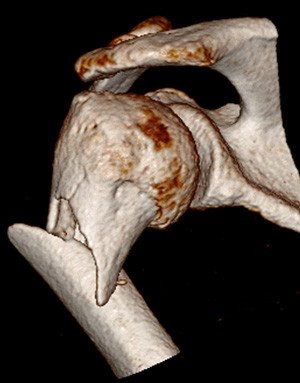

Schulternahe Knochenbrüche verursachen meist starke Schmerzen und Bewegungseinschränkungen. Eine Röntgenuntersuchung und gegebenenfalls auch Zusatzuntersuchungen wie eine Computertomographie bestätigen die Diagnose und sind unabdingbar für die Wahl der richtigen Therapie.

Ist es beim Unfall zu einer erheblichen Verschiebung der Knochenfragmente gekommen, sind die Chancen auf ein gutes Ausheilen und Wiedergewinnen der Schulterfunktion ohne Operation schlecht. Durch den chirurgischen Eingriff werden die einzelnen Knochenteile mittels Schrauben und Platten wieder in die korrekte Stellung und Achse zum restlichen Oberarm gebracht und fixiert. Wenige Tage nach dem Eingriff beginnt die Krankengymnastik damit das Risiko einer Einsteifung minimiert werden kann. Mit zunehmendem Alter verändert sich die Knochenqualität. Der Knochen wird fragiler und die Behandlung von Frakturen schwieriger. In gewissen Fällen kann die sichere Verankerung von Schrauben und Platten nicht mehr erreicht werden. Solchen Patienten ermöglicht das Einsetzen eines Kunstgelenks eine gute Option auf eine erfolgreiche Behandlung.